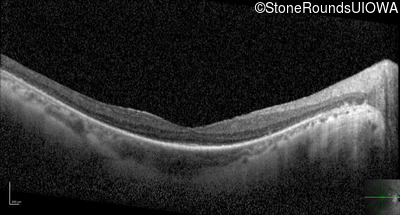

Optical Coherence Tomography - Right - 20/40 +1

Exemplar / OCT Stack